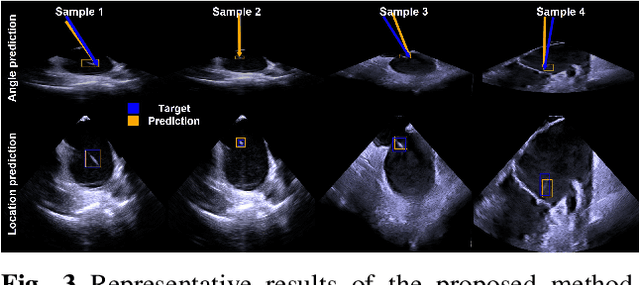

Abstract:Intra-cardiac Echocardiography (ICE) plays a critical role in Electrophysiology (EP) and Structural Heart Disease (SHD) interventions by providing real-time visualization of intracardiac structures. However, maintaining continuous visibility of the therapy device tip remains a challenge due to frequent adjustments required during manual ICE catheter manipulation. To address this, we propose an AI-driven tracking model that estimates the device tip incident angle and passing point within the ICE imaging plane, ensuring continuous visibility and facilitating robotic ICE catheter control. A key innovation of our approach is the hybrid dataset generation strategy, which combines clinical ICE sequences with synthetic data augmentation to enhance model robustness. We collected ICE images in a water chamber setup, equipping both the ICE catheter and device tip with electromagnetic (EM) sensors to establish precise ground-truth locations. Synthetic sequences were created by overlaying catheter tips onto real ICE images, preserving motion continuity while simulating diverse anatomical scenarios. The final dataset consists of 5,698 ICE-tip image pairs, ensuring comprehensive training coverage. Our model architecture integrates a pretrained ultrasound (US) foundation model, trained on 37.4M echocardiography images, for feature extraction. A transformer-based network processes sequential ICE frames, leveraging historical passing points and incident angles to improve prediction accuracy. Experimental results demonstrate that our method achieves 3.32 degree entry angle error, 12.76 degree rotation angle error. This AI-driven framework lays the foundation for real-time robotic ICE catheter adjustments, minimizing operator workload while ensuring consistent therapy device visibility. Future work will focus on expanding clinical datasets to further enhance model generalization.